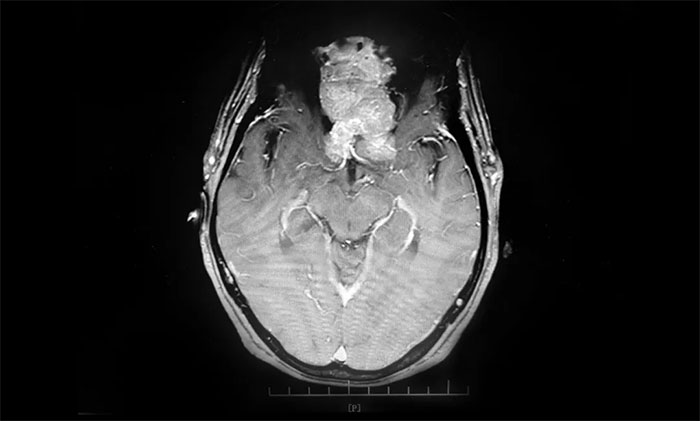

▲ 通过增强磁共振影像,可见前颅底嗅沟脑膜瘤,体积巨大

头部增强磁共振影像显示,患者前颅底嗅沟脑膜瘤体积约6.7*6.4*5.1公分,大如鸭蛋,属巨大脑膜瘤,瘤体一小部分已经延伸侵犯到筛窦内。经评估并充分告知手术风险后,7月9上午,李志强主任为患者实施巨大脑膜瘤切除手术。